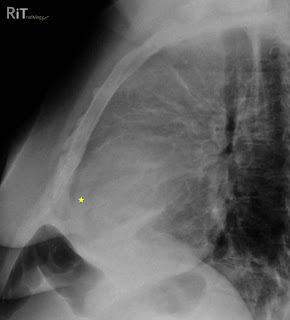

Figure 1: Lateral chest radiograph shows separation of the retrosternal (dark line parallel to the sternum anterior to the yellow star) and epicardial fat stripes (dark line behind the yellow star). This patient also has an anterior mediastinal mass due to lymphoma.

- Lateral view: separation of retrosternal and epicardial fat stripes by more than 2 mm (Oreo cookie sign)

- Oreo cookie sign: epicardial fat and retrosternal fat stripes = outer dark cookie layers; opaque fluid = white fluff of the cookie